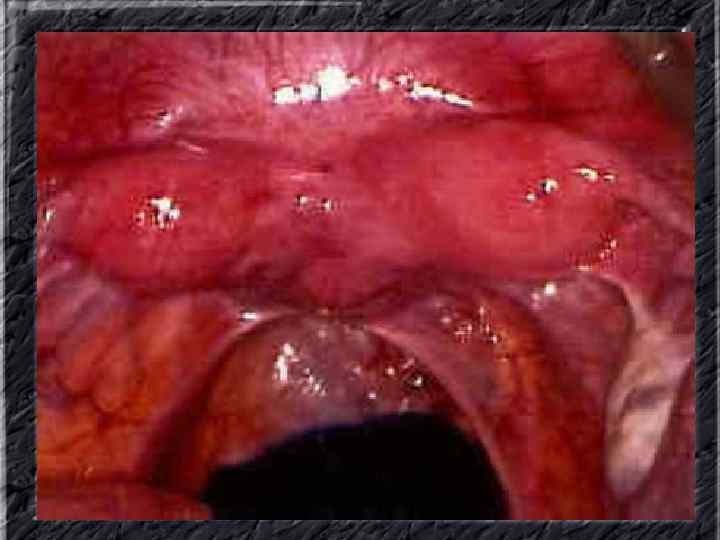

Названия слайдов: • • • Слайд 1. Титульный лист. Слайд 2. Лапароскопия: вид неизмененной матки. Слайд 3. Гистеросальпингография: тень полости неизмененной матки при ее заполнении рентгеноконтрастным веществом Слайд 4. Ультрасонография: вид эндометрия в разные фазы менструального цикла. Слайд 5. Матка: два отдельных тела имеют общую шейку; макропрепатат. Слайд 6. Гистерография: разделение тени полости матки выемкой, расположенной в области дна. Слайд 7. Лапароскопия: удвоение матки. Слайд 8. Ультрасонография: удвоение матки. Слайд 9. Гистерография: четкие неровные контуры дефектов наполнения полости матки при синехиях. Слайд 10. Эндометриальная гиперплазия: полость матки выстлана пышным, подобным пальмовым листьям гиперпластическим эндометрием; макропрепарат.

Названия слайдов: • • • Слайд 20. Ультрасонография: диффузная эхонеоднородность миометрия при внутреннем эндометриозе. Слайд 21. Эндометриоз матки: Пять маленьких очажков эндометриоза красно-коричневого цвета по задней поверхности матки; макропрепарат. Слайд 22. Множественная миома матки: видны субсерозные, субмукозные и интрамуральные узлы; макропрепарат. Слайд 23. Большая миома матки, подвергшаяся дегенеративным изменениям ( «красная дегенерация» ); макропрепарат. Слайд 24. Ультрасонография: интрамуральный узел фибромиомы, деформирующий контуры органа. Слайд 25. Ультрасонография: интрамуральный узел фибромиомы, деформирующий полость матки и смещающий эндометрий книзу. Слайд 26. Ультрасонография: субсерозный узел фибромиомы матки с эхопризнаками нарушения питания. Слайд 27. Лапароскопия: субсерозная фибромиома матки. Слайд 28. Лапароскопия: выраженный сосудистый рисунок на поверхности субсерозной фибромиомы матки. Слайд 29. Лапароскопия: выраженный сосудистый рисунок на поверхности субсерозной фибромиомы матки. Слайд 30. Большая цервикальная плоскоклеточная карцинома, которая простирается до влагалища; макропрепарат.

Названия слайдов: • • • Слайд 51. Ультрасонография: интерстициальный и истмический отделы маточной трубы. Слайд 52. Лапароскопия: неизмененная правая маточная труба. Слайд 53. Ультрасонография: многокамерная форма сальпингита. Слайд 54. Лапароскопия: относительно равномерное утолщение маточной трубы при гидросальпинксе. Слайд 55. Лапароскопия: вид маточной трубы при гидросальпинксе. Слайд 56. Гистеросальпингография: неравномерное расширение и деформация маточных труб. Слайд 57. Прервавшаяся трубная беременность: плод; макропрепарат. Слайд 58. Гематосальпингс, развившийся вследствие внутреннего разрыва плодо-вместилища при трубной беременности; макропрепарат. Слайд 59. Лапароскопия: значительное увеличение участка маточной трубы при трубной беременности. Слайд 60. Лапароскопия: скопление крови в полости малого таза в результате трубного аборта.

Названия слайдов: • • • • Слайд 61. Лапароскопия: множественные спайки в полости малого таза женщины. Слайд 62. Лапароскопия: признаки спаечной болезни в полости малого таза женщины. Слайд 63. Лапароскопия: деформация маточной трубы при спаечном процессе в полости малого таза. Слайд 64. Ультрасонография: спаечный процесс в малом тазу. Слайд 65. Ультрасонография: мультифолликулярные яичники. Слайд 66. Ультрасонография: кистома яичника. Слайд 67. Ультрасонография: патолоргия эндометрия. Слайд 68. Ультрасонография: внематочная беременность. Слайд 69. Ультрасонография: внематочная беременность. Слайд 70. Кольпоскопия: кандлилома – папиллома. Слайд 71. Кольпоскопия: кандлидозные бели. Слайд 72. Кольпоскопия: полип шейки матки. Слайд 73. Кольпоскопия: эрозия шейки матки. Слайд 74. Кольпоскопия: экспульсия ВМС.